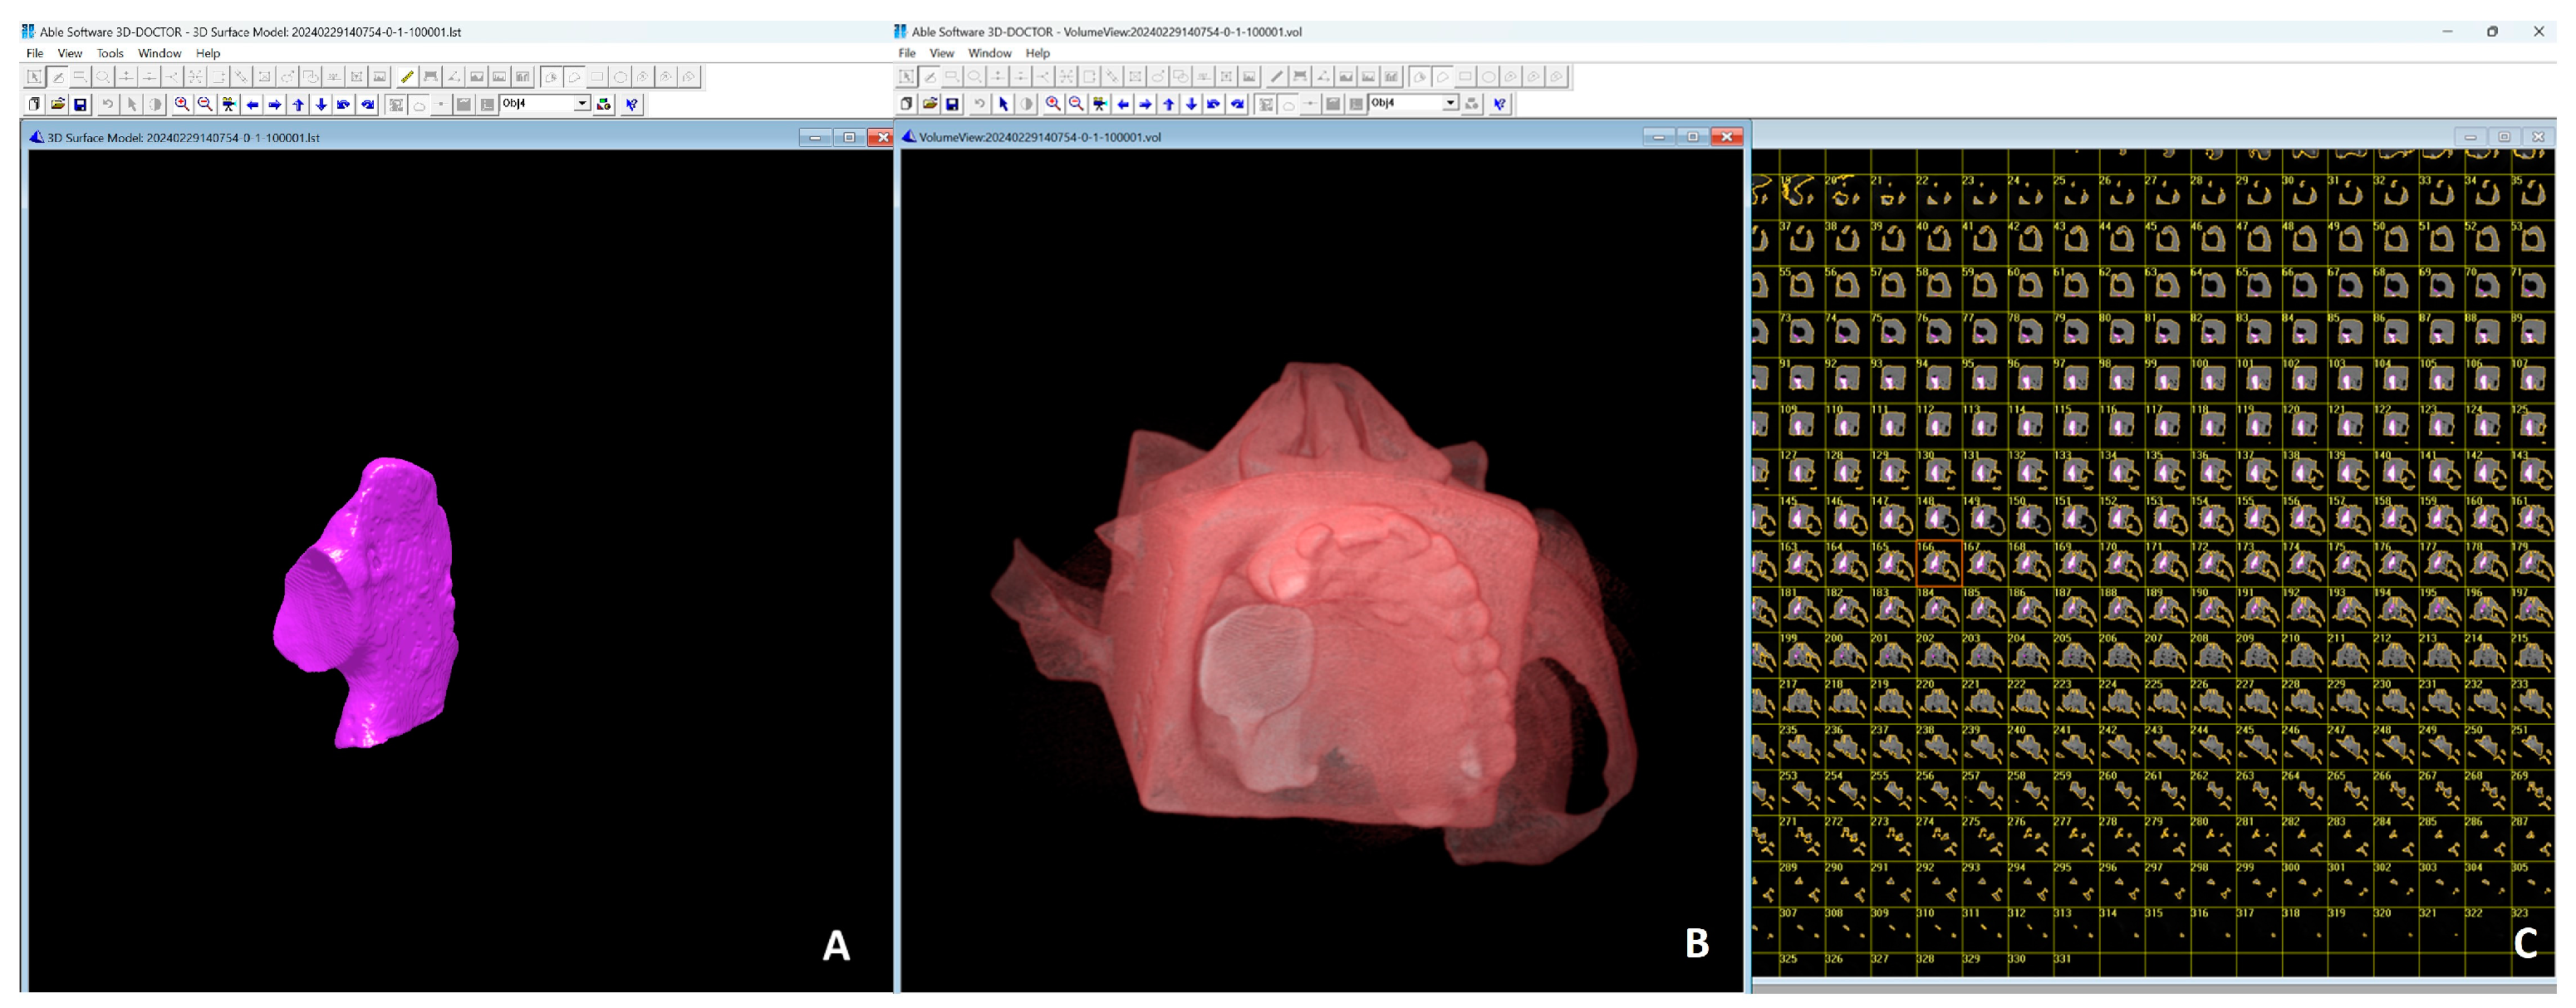

2. Materials and Methods